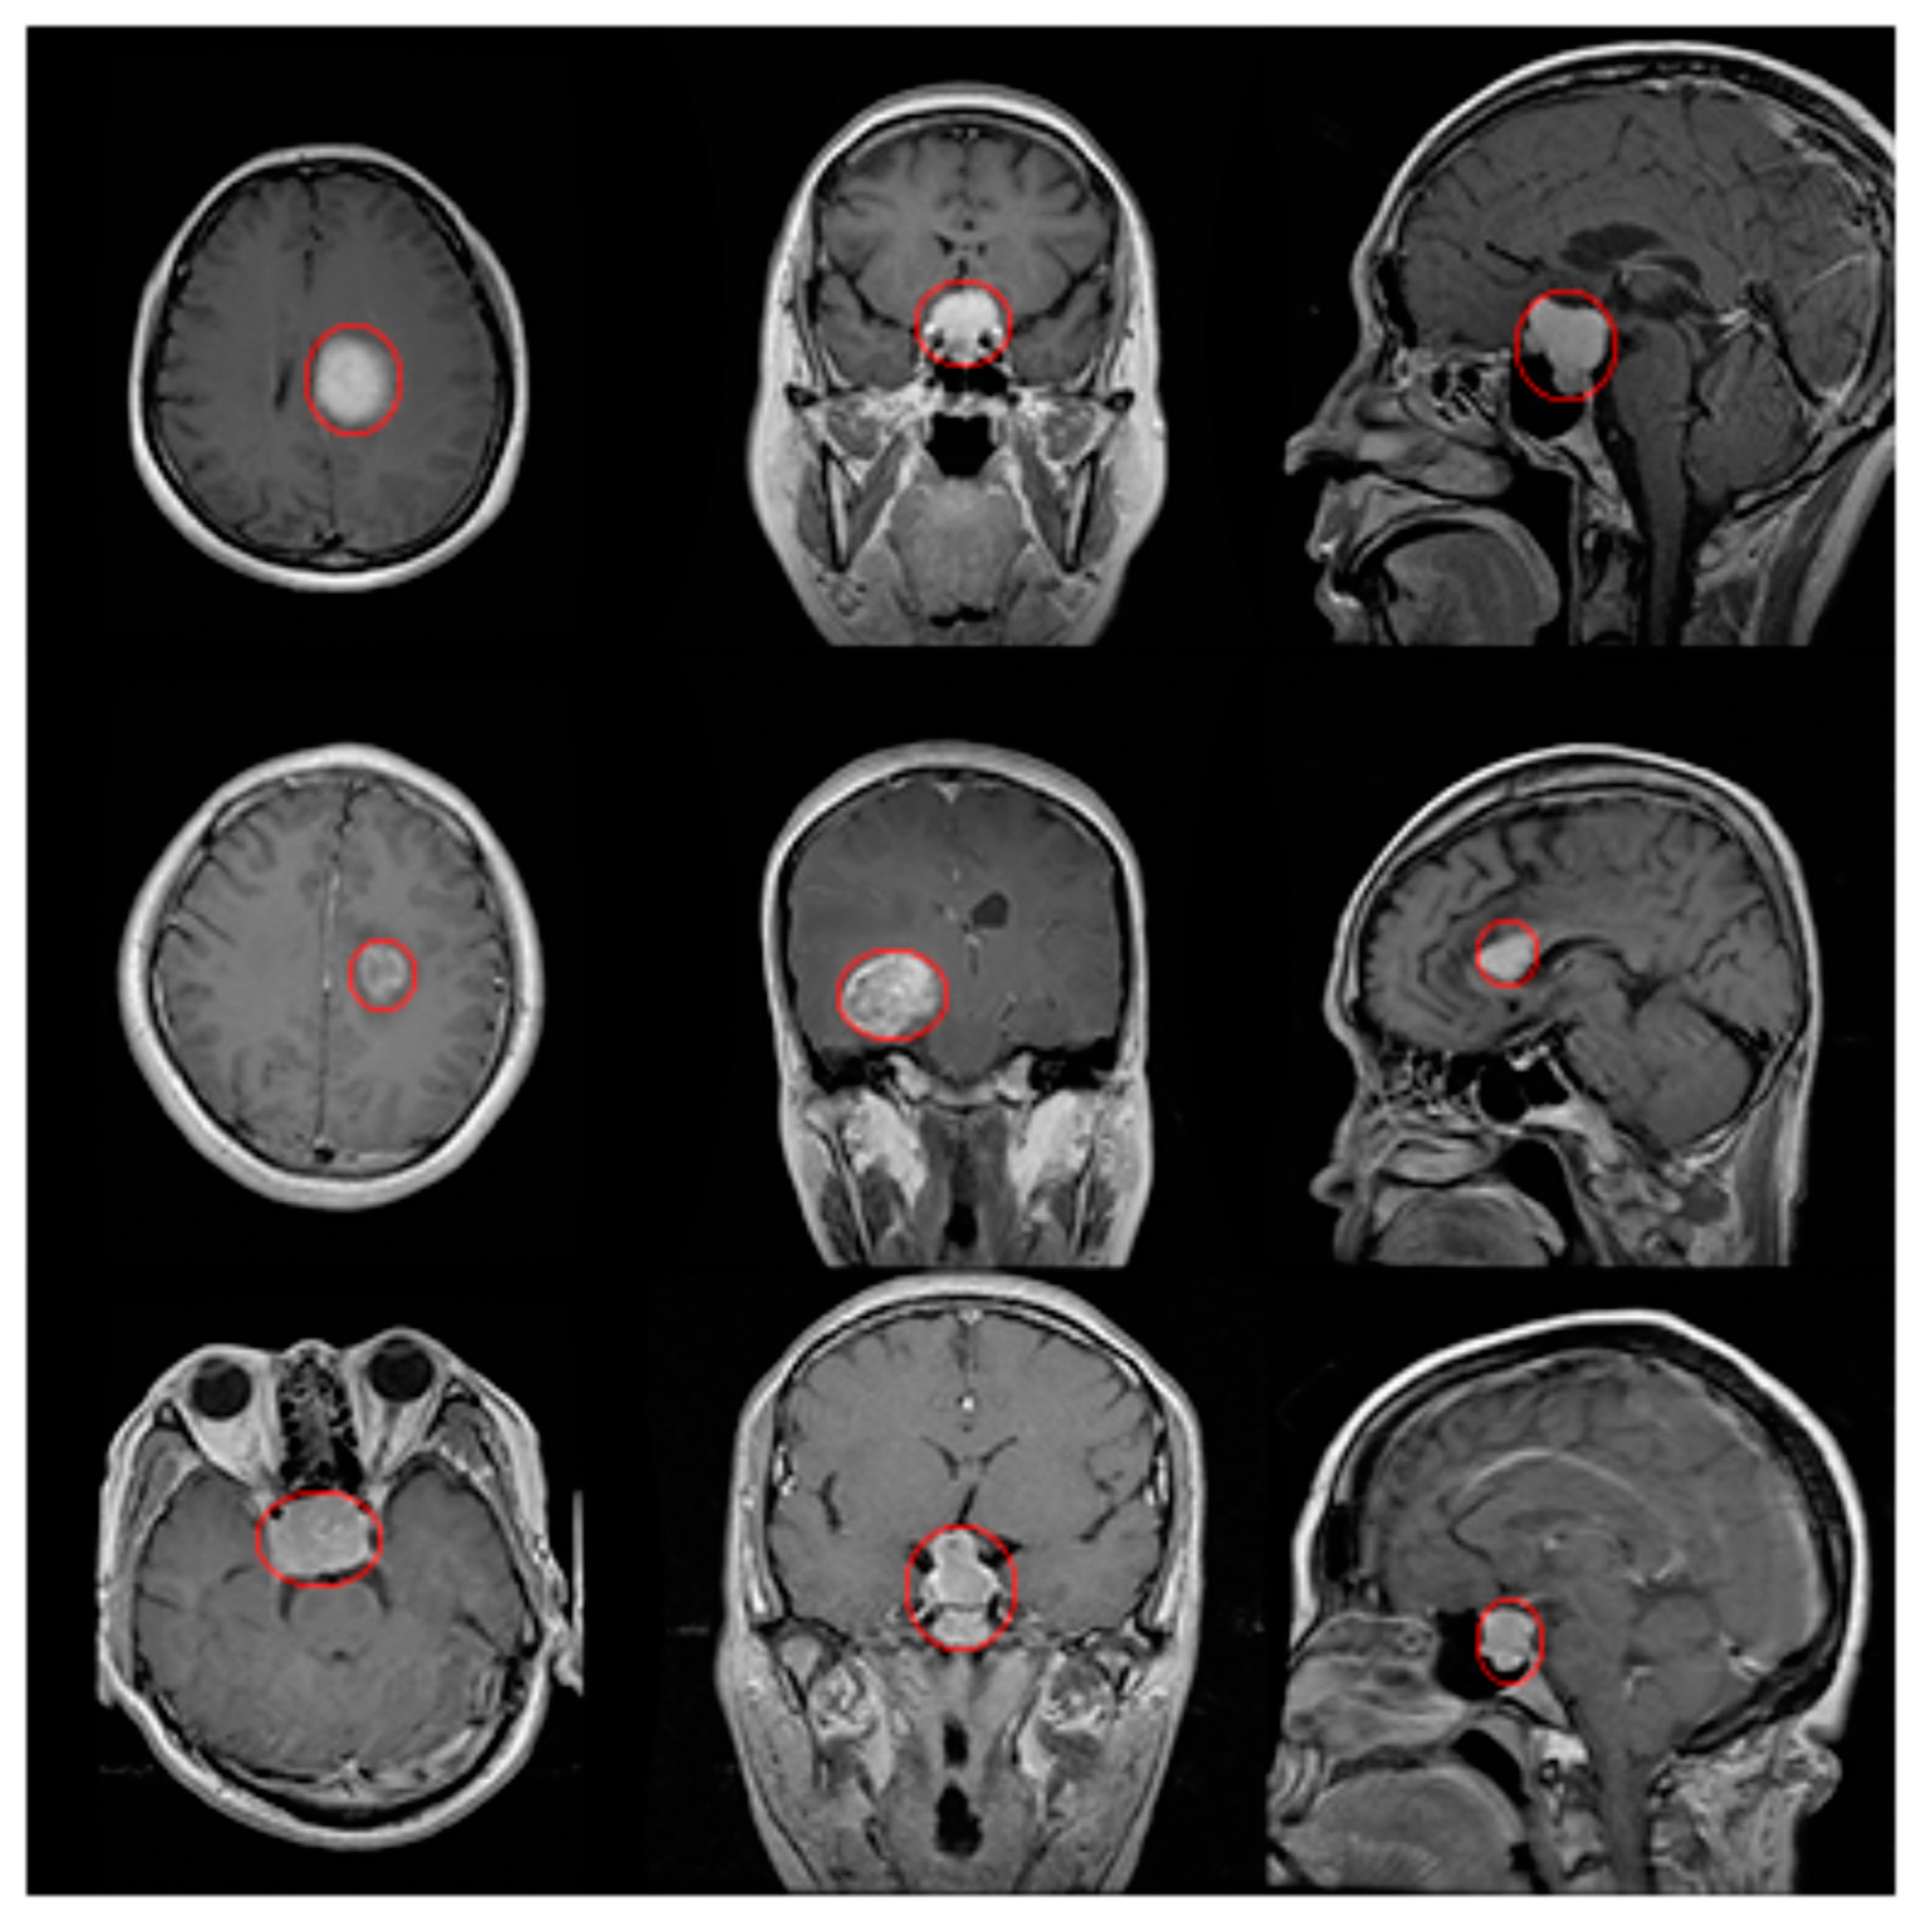

4. Experimental Results

| Tumor Type/Plane | Axial | Coronal | Sagittal |

|---|---|---|---|

| Meningioma | 0.913 | 0.923 | 0.985 |

| Glioma | 0.939 | 0.940 | 0.986 |

| Pituitary | 0.947 | 0.943 | 0.909 |